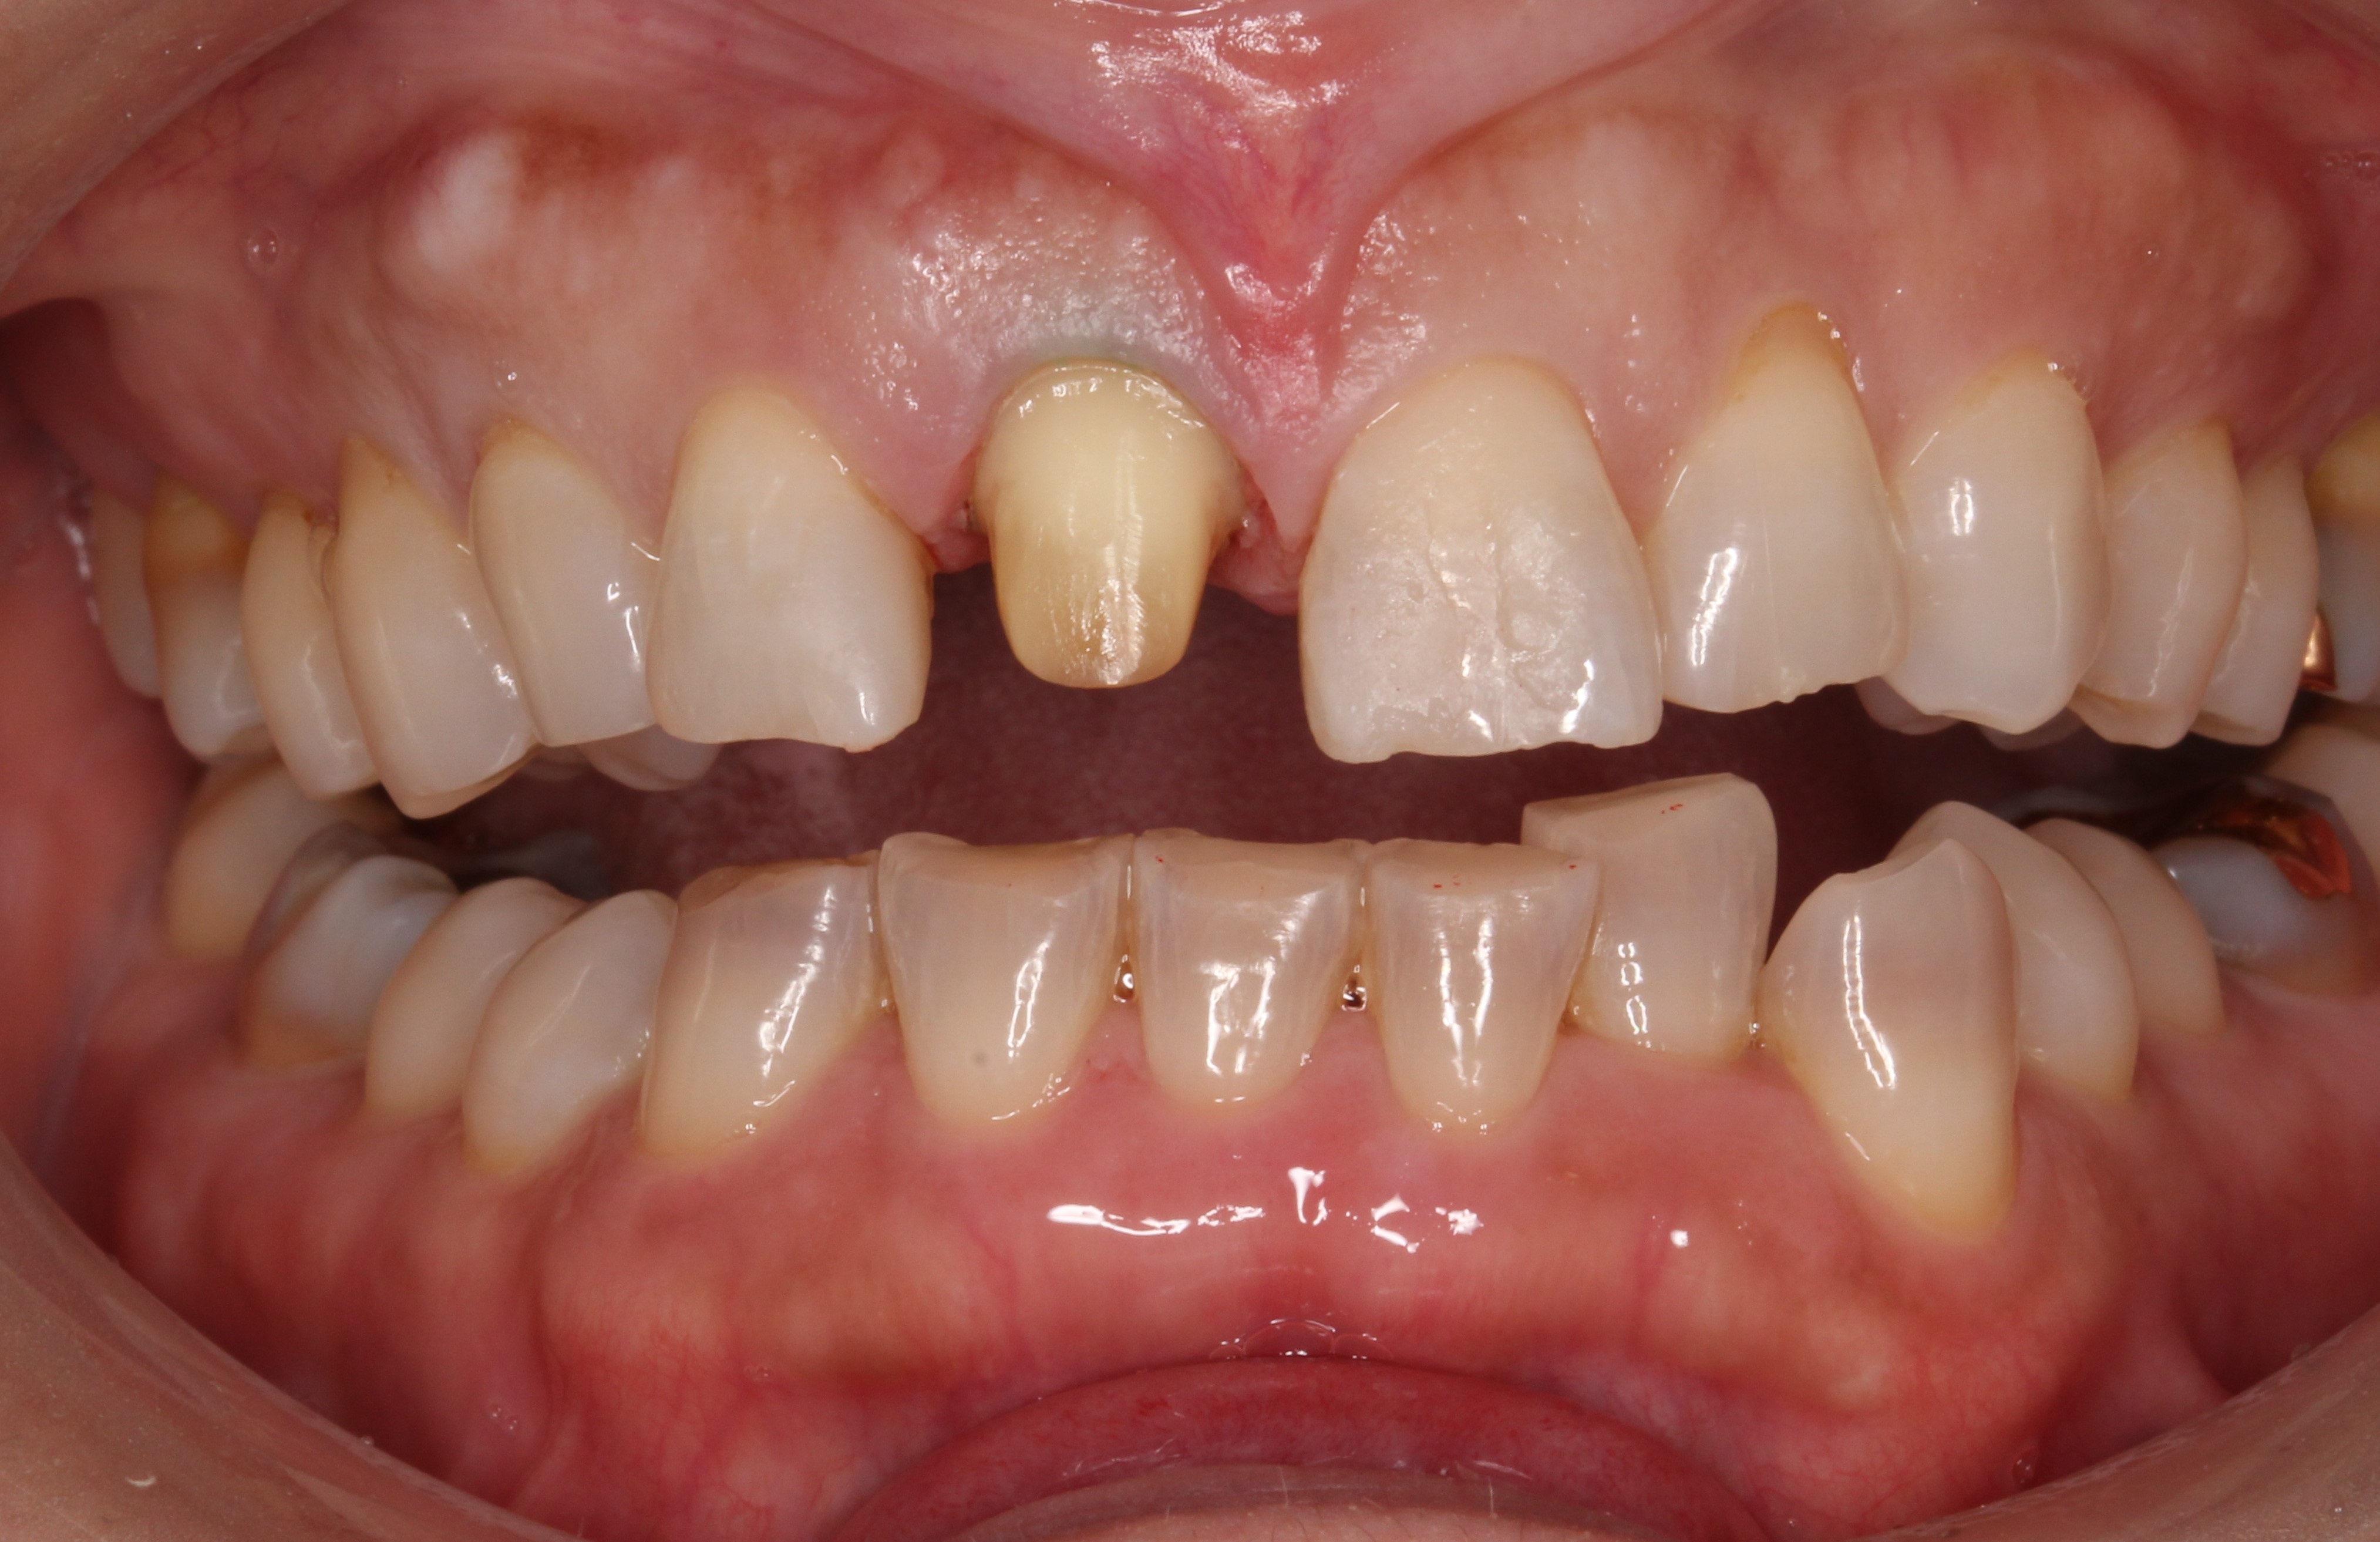

被せものを外し、歯の形を整えていきます。

被せものがしてある歯は一回り小さく山型に削ってあります。

通常被せものは小さくした歯に被せていきます。

今回の患者さんは、テトラサイクリン歯といって元々、色の濃淡がある歯のグラデーションをしています。よく見ると上の歯と下の前歯の色が違います。

このように特徴があるグラデーションを合わせていくのは技術的に難しくなります。